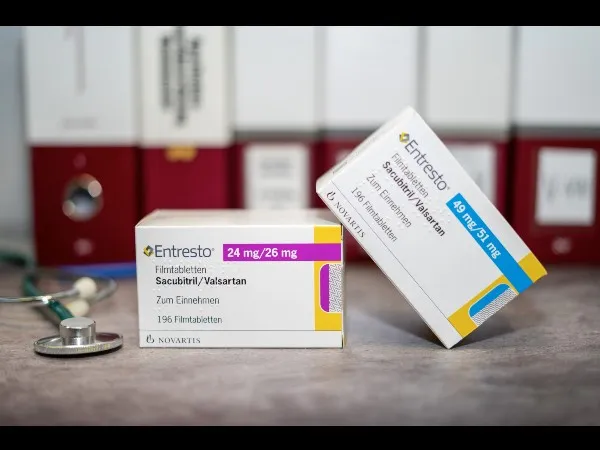

O paciente está congesto? O que realmente ajuda na prática?

O paciente está congesto? O que realmente ajuda na prática?